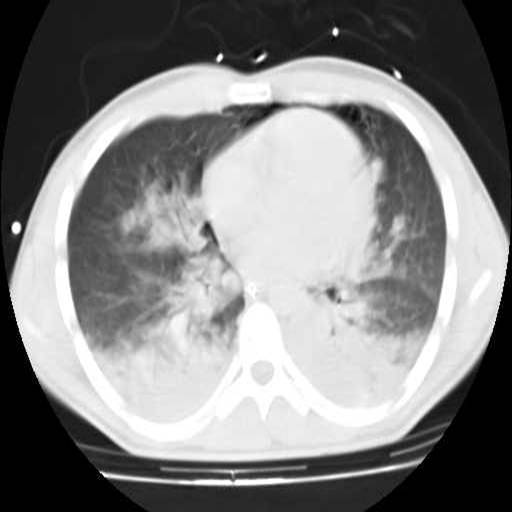

![]() |

| Predominio de las opacidades en la región pulmonar posterior en un paciente con neumonía grave https://remi.uninet.edu/2004/07/REMIC21.htm |

En el paciente grave, que generalmente se encuentra en decúbito supino, la zona posterior del tórax es la más cercana al suelo y, por tanto, la que recibe mayor presión hidrostática, contrario a lo que ocurre en las zonas anteriores (que se encuentran arriba), donde hay mucha menos sangre, pero más aire. Además, cuando existe una enfermedad pulmonar restrictiva (como la neumonía) hay tendencia al colapso alveolar, limitando la cantidad de aire que pueden albergar. En ocasiones, solo se da el intercambio en un cuarto del pulmón. Es en esta situación cuando tiene sentido la pronación.